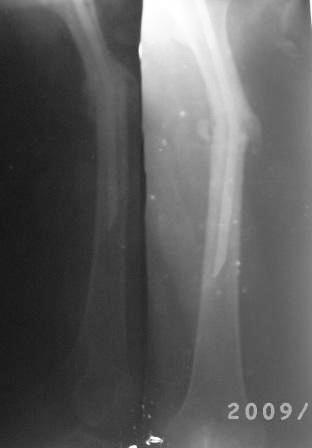

Снимки не очень качественные, почему-то все снимки такие . видимо поступило партия некачественных пленок.

12.02.09г б-ная оперирована: з/остеоклазия (без особого труда- видимо тугой ложный сустав) коррекция деформации, удаление штифта из надвертельной обл, рассверливание канала гибкими развертками, реостеосинтез блокируюшим гвоздем Д-11мм.

P.S. Снимки не качественные, извиняюсь! последний снимок ЭРГА, два снимка объединил.

Я заранее приношу свои извинения, но по демонстрации видно, что сама методика БИОС использована с нарушениями. Да я с Вами согласен и сам часто встречался подобными случаями, когда из-за отсутствия функции конечности (опорной и двигательной) поврежденный сегмент теряеть минеральную плотность, тем самым развивается остеопороз. Однако Вам надо было заранее учитывать эти моменты и дистальные винты надо было установить четко бикортикально, в Вашем случае верхний дистальный винт короткий, нижний дистальный винт вне отверстия, в таком расположении он никак не может быть в блокирующем отверстии. Ранняя опорная нагрузка зависит от стабильности синтеза, веса пациента, но в любом случае дозированная нагрузка (собственный вес конечности) нужна, иначе срастить ложный сустав и ликвидровать остеопороз невозможно (кость должна выполнять свою функцию). С уважением Ерсин Жунусов.